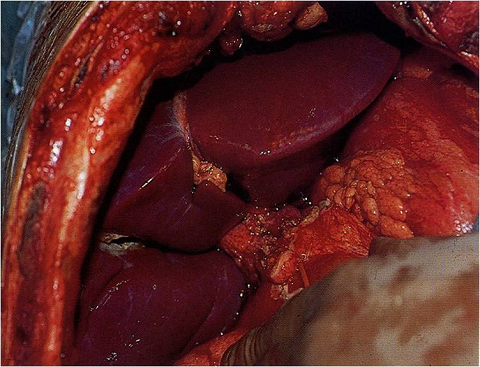

Laparoscopic Liver, Pancreas and Bilary Surgery

- Liver resection (for cancer and other liver tumor)

- Splenectomy (for removal of the spleen)